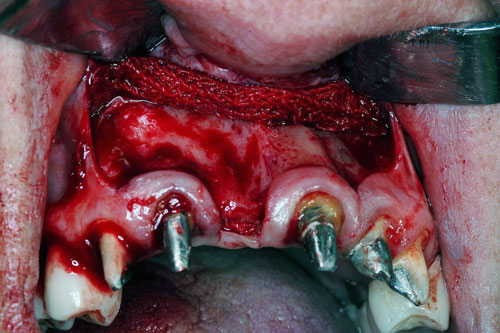

Mientras dichos movimientos ortopédicos se producen (período que supondrá otros seis meses), estudiamos los actos quirúrgicos a realizar en los cuatro implantes que pondremos. De acuerdo al estudio Desatascan realizado observamos tres situaciones diferentes: 1º-El Primer Molar Inferior Izquierdo, lo instalamos mediante Cirugía Minimamente Invasiva , con la aplicación de una Férula Quirúrgica Obtenida de los datos del scanner tratados con un programa de CMI (Cirugía Minimamente Invasiva), previa prueba en un modelo estereolitográfico, ya que la altura ósea era apenas de 9 mm. 2º- El Primer Molar Superior Derecho, se implantará mediante una ligera Elevación Atraumática (Trans alveolar) de Seno una vez logrado el espacio mesio distal necesario. 3º- El Incisivo Central Superior Derecho ausente, cuenta con un sustrato óseo prácticamente inexistente. El espesor de la tabla era de menos de 2 mm. Los caminos posibles a seguir para contar con una Rehabilitación de piezas independientes son dos: Optamos por esta segunda opción por ser menos cruenta y no necesitar de una zona dadora. Técnica esta que pondremos en práctica en dos etapas diferidas: 1º-Incisión horizontal palatinizada, incisiones peri rodetes gingivales e incisiones de descarga. Dilatación que comenzamos con dos incisiones de descarga sobre la cortical vestibular realizadas con disco. y el comienzo de la dilatación propiamente dicha mediante una hoja de bisturí, para luego seguir con un periostótomo . Recién después de alcanzada una cierta separación de la cortical vestibular de la palatina, empezamos con los dilatadores roscados. En este punto podríamos haber utilizado sin riesgos un Implante de 3,8 mm de diámetro, pero a fin de mejorar la estética del pilar emergente decidimos rellenar con material osteoconductor y osteoinductor (BiOss) y cubrir mediante membrana reabsorvible ( Bio Guide). 2º-Implantación seis meses después. Mientras se van cumpliendo los tiempos antes mencionados, y comprobamos reiteradamente la funcionalidad de la oclusión con los provisorios, tomamos impresiones definitivas y construimos primero el maxilar inferior, para definir en primer término la porción inferior de la Guía Anterior., y a nivel posterior Curvas y Microplanos. Para luego realizar los cuadrantes premolar- molar del superior: La espera de la regeneración ósea y sus tiempos pertinentes, más la espera de los tiempos de la implantación, nos obligaron a modificar las etapas del protocolo D.AT.O de manera de mantener la –D- mediante el sector superior de la GA. en provisorios, mientras fuimos resolviendo en forma definitiva los demás sectores. Ya pasados los meses necesarios para recrear un hueso adecuado en el área del Incisivo Superior Derecho, procedemos a resolver la implantación de dicha zona, observando que todo el esfuerzo dedicado al mismo había sido inútil, ya que la formación de hueso se produjo minimamente. Cuatro meses después tomamos impresiones del sector Antero Superior de la Guía Anterior, incluyendo el arrastre de un transfer . Seguimos modelando la encía con un nuevo juego de provisorios. Y se construye entonces el sector superior de la Guía Anterior. Se efectúa un control radiográfico a los 6 meses. Se ha intentado mostrar en esta Rehabilitación, que a pesar de las distintas circunstancias de cada paciente, siempre debemos tener en cuenta la necesidad de ejercer la DESOCLUSIÓN del caso como prioridad número uno, para luego perseguir la ALINEACIÓN TRIDIMENSIONAL de las arcadas y obtener así una OCLUSIÓN equilibrada. D.AT.O. ES EL PROTOCOLO QUE DEBEMOS SEGUIR EN TODA REHABILITACIÓN. BIBLIOGRAFÍA 1)William Mc Horris,B.S.,D.D.S. Oclusión. Con especial énfasis sobre :El rol funcional y parafuncional de los dientes anteriores. 2)Von Spee , Craff(Anatomista alemán, describió la curva de compensación de la articulación de molares y premolares).CURVA DE SPEE 1.89 3)Stuart,D.”Some aspects of the inervation teeth.”Procedings of Royal Society of Medicine.20:1675,19274)Muhleman,H. y Savdir,S”Tooth movility-its causes and significance”Journal of Periodontology ,36:153,Marzo ,Abril,1965. 4)Muhleman,H. Y Savdir,S”Toothmovility its causes and significance” Journal of Periodontology,36:153,marzo,abril,1965. 5-Oclusión y Diagnóstico en Rehabilitación Oral. 6-Anatomia Odontológica. 7-A contribution to the study of the movementes of the mandible. 8-Celenza F.W, Nadeskin J.F.,Oclusión.Situación actual. 9-D´Amico 10-Dawson P.E. 11-Huffman –Regenos. 12-Hobo S.-Takayama H.A. 13-Lucia V.O 14-Mc Horris. 15-Mc Horris. 16-Stuart C. 17-Vartan Veshnilian 18-Alvarez Cantoni H. AUTOR:Ratificación del Protocolo en Rehabilitación Bucal a pesar de las incidencias propias de cada caso clínico. A propósito de un caso.

Verificamos también el escaso ancho crestal, lo que nos obliga a utilizar dilatadores roscados y un osteótomo para elevar inicialmente la membrana de Schneider.

Elevación de membrana mediante periostótomo

Elevación de membrana mediante periostótomo